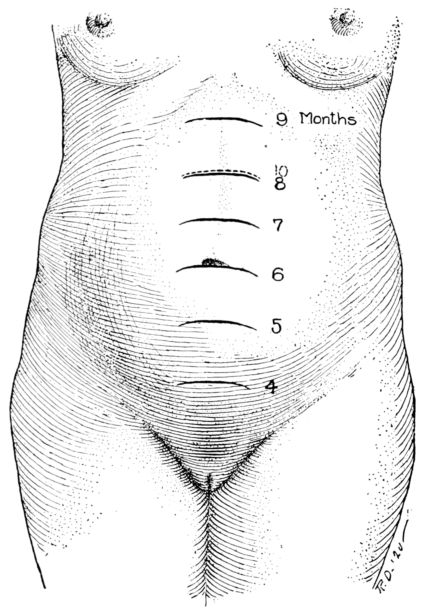

| 31. | Height of fundus at different stages of pregnancy | 94 |

| 32. | Contour of abdomen at ninth month | 95 |

| 33. | Contour of abdomen at tenth month | 95 |